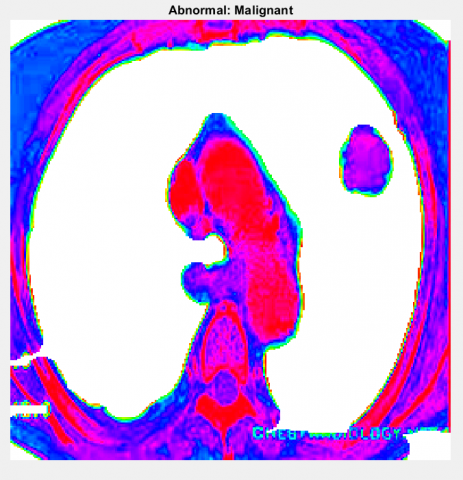

Region wrapping is the step of operations which eradicate incorrect boundaries and bogus regions by merging adjacent regions based on the gray value of these regions. Region wrapping is accomplished to group the tumor regions detected together as single layer of region after the thresholding. The complete segmentation results of each stage are illustrated in Figure 2.

(a) Original lungs image

(b) SLIC -Cancer segmented

(c) Optimal Thresholding (Enhanced image)

(d) Region Wrapping-abnormal malignant

Figure 2. Segmentation Results: a) Original Image; b) SLIC; c) Optimal Thresholding; d) Region Wrapping

In Figure 6, we shown the result of preprocessing stage, in which we used gamma correction-based image enhancement to improve the contrast of original image and that also clearly depicted in the above Figure 6. Next implementation is that segmentation of brainy region means removal of skull content available in the whole image as shown in Figure 7.

Once the gray segmentation output is obtained, we are performing pseudo color transformation using labelling method in morphological operations. This transformation will retain the highly infected regions if any in the segmented lungs cancer area. The output of segmented and pseudo color converted is illustrated in Figure 6.

Figure 6. Segmented image and pseudo color transformed image

Figure 6 shows the final result of lungs cancer detected content the classification results from our proposed method of ICCAN. Figure 7 is shown for the pictorial representation of performance comparison of our proposed with the existing algorithms of researches [28-31]. Table 1 is for numerical comparison.

Figure 6, shows the final result of tumor detected content the classification results from our proposed method of ICCAN.